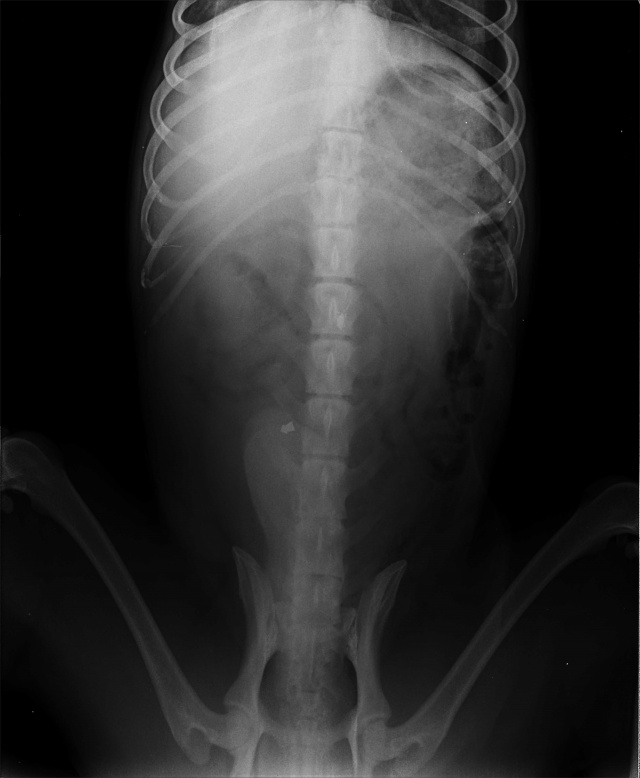

16530 - Maardu/ TONY

- Возраст: 10 лет

Vigastatud. Tulistatud õhupüssist, üks kuul kõhu sees ja teine selgroos.